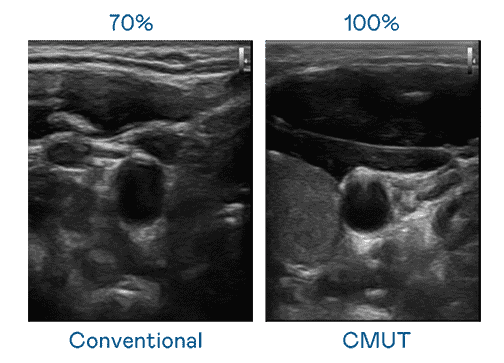

CMUT 技术是一种用电容式微机电元件来产生超音波讯号的技术。。与传统 PZT 压电式技术相比,,,CMUT 频宽增加 30%,,更宽频的超音波讯号让影像解析度大幅提升,,是实现高影像品质医疗超音波扫描、、、促进精准医疗发展的关键技术。。

大频宽带来超清晰影像

超音波影像的解析度高低,,,首先取决于探头能发出的讯号频宽。。。。尊时凯龙 CMUT 可提供高清晰的超音波讯号,,提供高频宽、、、、高灵敏度、、、影像纹理细节更高的超音波影像,,协助医护人员缩短影像判读时间及利用精准的医疗影像进行诊断。。。